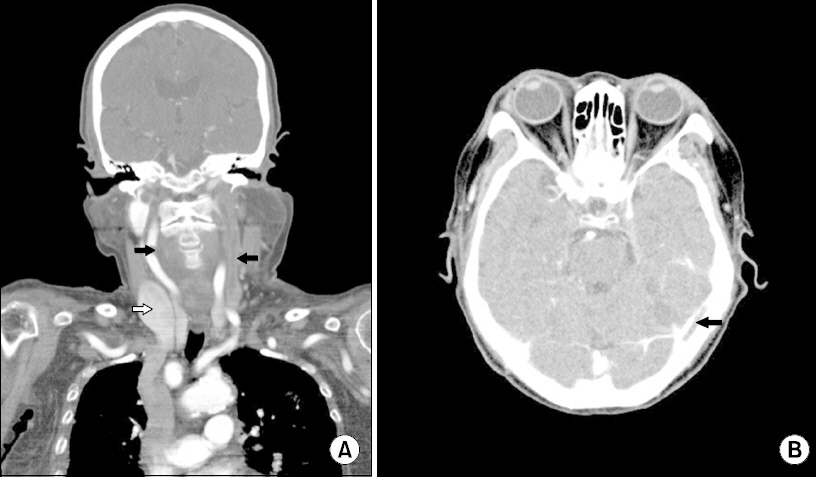

- A 70-year-old woman with an infectious thrombus in her left internal jugular vein (IJV) underwent carotid endarterectomy for stenosis and a highly movable plaque in her right carotid artery. She had been treated with antibiotics for four weeks before surgery due to Lemierre syndrome, a rare septic thrombophlebitis in the IJV secondary to an oropharyngeal infection. The right IJV was in a two-fold dilated state due to compensation for a thrombotic left IJV. Accordingly, superficial cervical plexus block was performed under ultrasound guidance to ensure safety and accuracy. During surgery, the alertness was maintained and the patient did not complain of pain in the absence of additional analgesics. No block-related complications were encountered. The authors report for the first time their regional anesthetic experiences in a patient with Lemierre syndrome.